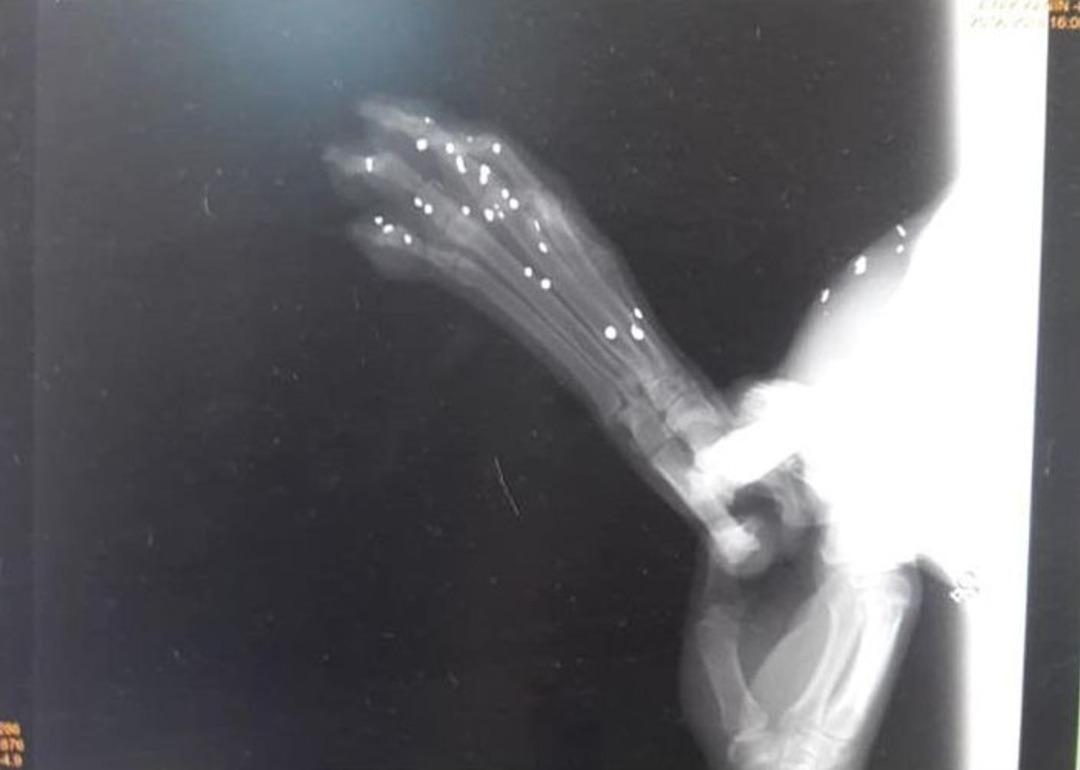

Muğla’nın Milas ilçesinde bir sokak köpeği ateşli silah saldırısı sonucu ayağından yaralandı. Yaralı hayvan, barınak yetkilileri tarafından bulunduğu yerden alınarak, tedavisi için veteriner kliniğine götürüldü.Milas’a bağlı Güllük Mahallesi’nde Orjan Sitesi ile Güllük Limanı girişi arasında hayvansever E.T. tarafından fark edilen yaralı köpek, durumun barınak yetkililerine bildirilmesiyle bulunduğu yerden alınarak, Bodrum’da özel bir veteriner kliniğine götürüldü. Yaralı halde bulunan köpeği veterinere götüren barınak yetkilileri köpeğin röntgeninin çekilmesinin ardından gördükleri manzara karşısında şoke oldu. Köpeğin yapılan muayenesinde ve çekilen röntgen sonucunda ayağından ateşli silah saldırısı sonucu yaralandığı tespit edildi.Yapılan muayenenin ardından durum Güllük Jandarma Komutanlığı’na bildirilmesiyle olayı gerçekleştiren kişi ya da kişilerin yakalanması için bölgede soruşturma ve inceleme başlatıldı. Bu vahşeti gerçekleştirenlerin kişi ya da kişilerin insanlığından şüphe edilmeli diyen Güllüklü hayvansever; “Olayla ilgili bilgisi olan herkesten yardımcı olmalarını, tanıklık yapmalarını rica ediyoruz. Sessiz kalmak suça ortak olmak demektir. Bunun peşini bırakmayacağız, Yine o bölgede geçtiğimiz haftalarda zehirlenen köpeğimizle ilgili de araştırmalarımız da sürüyor. Suçlu ya da suçluların bulunup cezalarını çekmesi için, bilgisi olan herkesten yardımcı olmalarını tekrar tekrar rica ediyoruz” dediler.